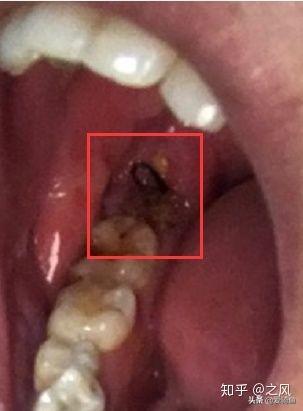

拍好片子后,去就診,房間里一個(gè)主治醫(yī)生,一個(gè)年輕女幫手,主治醫(yī)生看片子廢話不多說,安排你躺下,燈照著你,告訴你別緊張,說“緊張就別拔了”,然后打麻藥,三分鐘左右吧右下半部分臉就麻木了。然后拿一個(gè)錘子一個(gè)鑿子,砰砰砰鑿、撬起來了,雖然不疼但這陣仗會(huì)讓人緊張起來,然后醫(yī)生就會(huì)說你,”別緊張,放松,越緊張?jiān)诫y拔“,估計(jì)不到2分鐘一顆智齒就給拔下來了,然后半分鐘給你縫了線。 給你塞了一個(gè)止血棉讓你咬住。

黑線縫合傷口